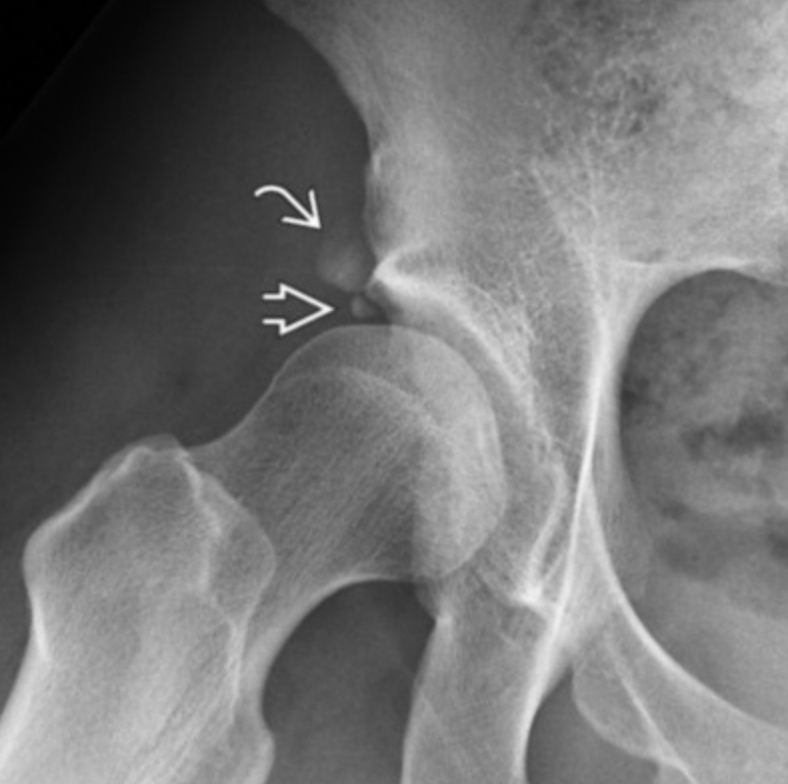

Developmental Dysplasia of the Hips

• Shallow acetabuli

• Normal acetabular angle <30

• Femur can’t sit in acetabuli, uncovered laterally

• Sourcil (superior-lateral acetabular roof) is underdeveloped and not downturned

• Small osseous fragment that looks similar but not exactly like an os acetabuli due to mineralization of the labrum

• Wiberg angle